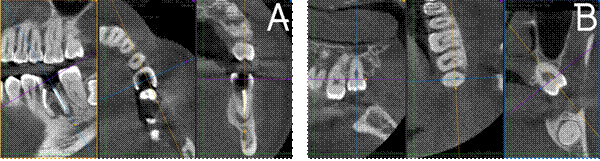

Se realizó una tomografía computarizada de

haz cónico (CBCT), con el fin de medir las dimensiones del hueso receptor

(Figura 2A), y analizar los terceros molares presentes para seleccionar la raíz

con mejor adaptación al alveolo receptor; resultando el órgano dental 28 como

el donador seleccionado (Figura 2B).

Figura 2.

Medidas de las zonas de interés obtenidas mediante CBTC. A) Corte

sagital, coronal y axial de la zona del alveolo receptor. B) Corte sagital,

coronal y axial del diente donador 28.